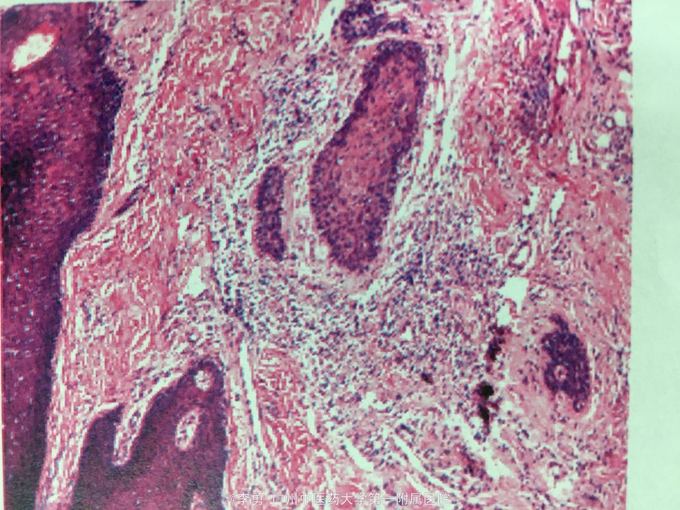

口周、四肢多发淡红斑基础上的浅溃疡、结痂,周围可见溃疡愈合后遗留的萎缩性疤痕、色素脱失。 病理活检:表皮增生、增厚伴轻度角化过度及角化不全,局部见浆痂,毛囊见明显角质栓形成,皮脚延长,真皮乳头部及浅层胶原变性,伴散在慢性炎细胞浸润。